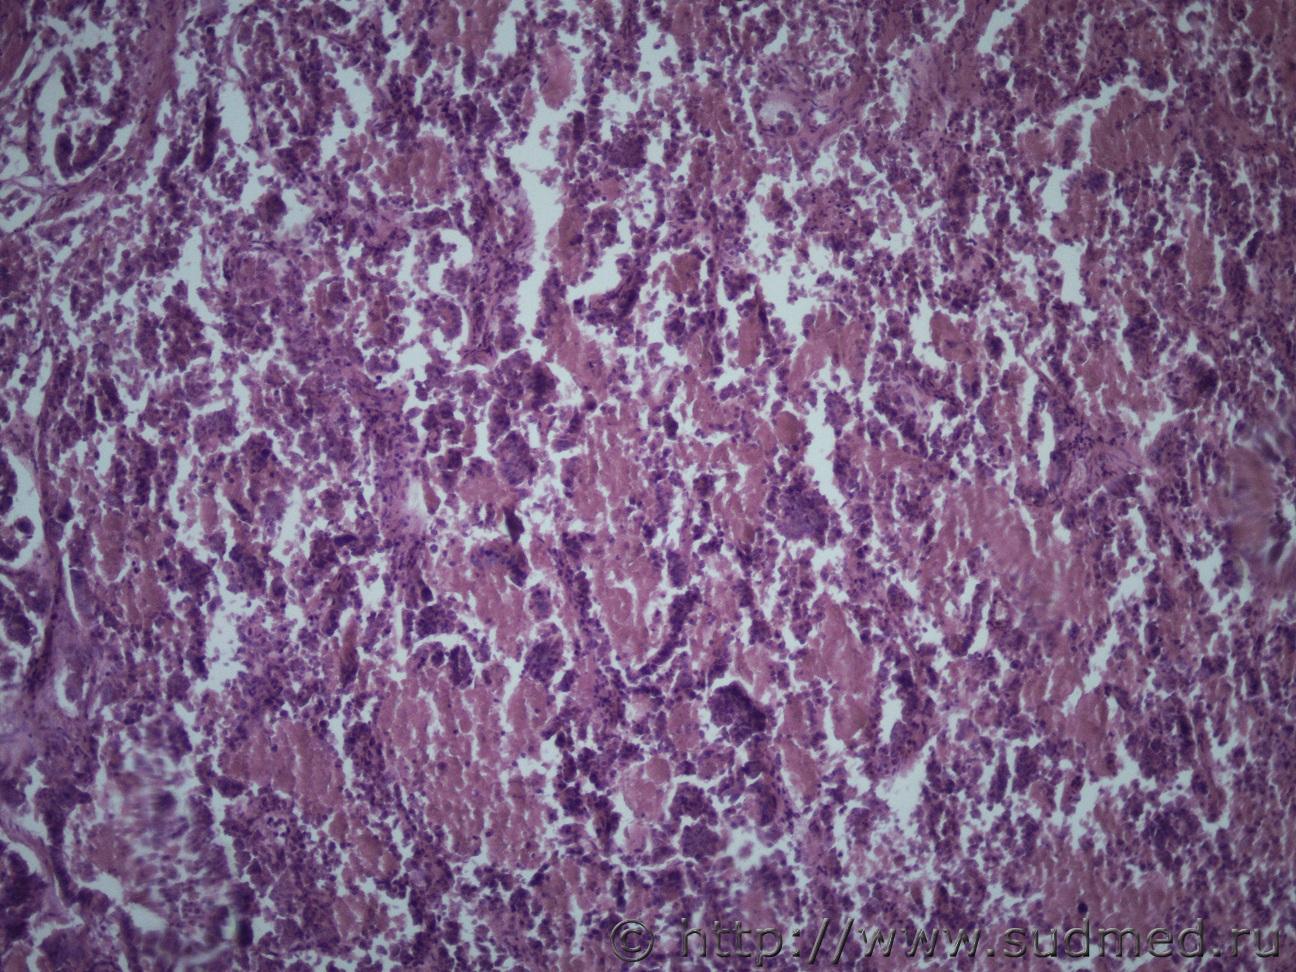

опухоль печени |

IVANNES опухоль печени 21.11.2018 - 10:39

Anton Эпителий желчного типа, д.б. холангиокарцинома. 21.11.2018 - 14:02

Медик Резекция почки (причина неизвестна).

andy_bob Железистая ткань с фигурами патологического митоза... 29.11.2018 - 12:39![]() ![]() |